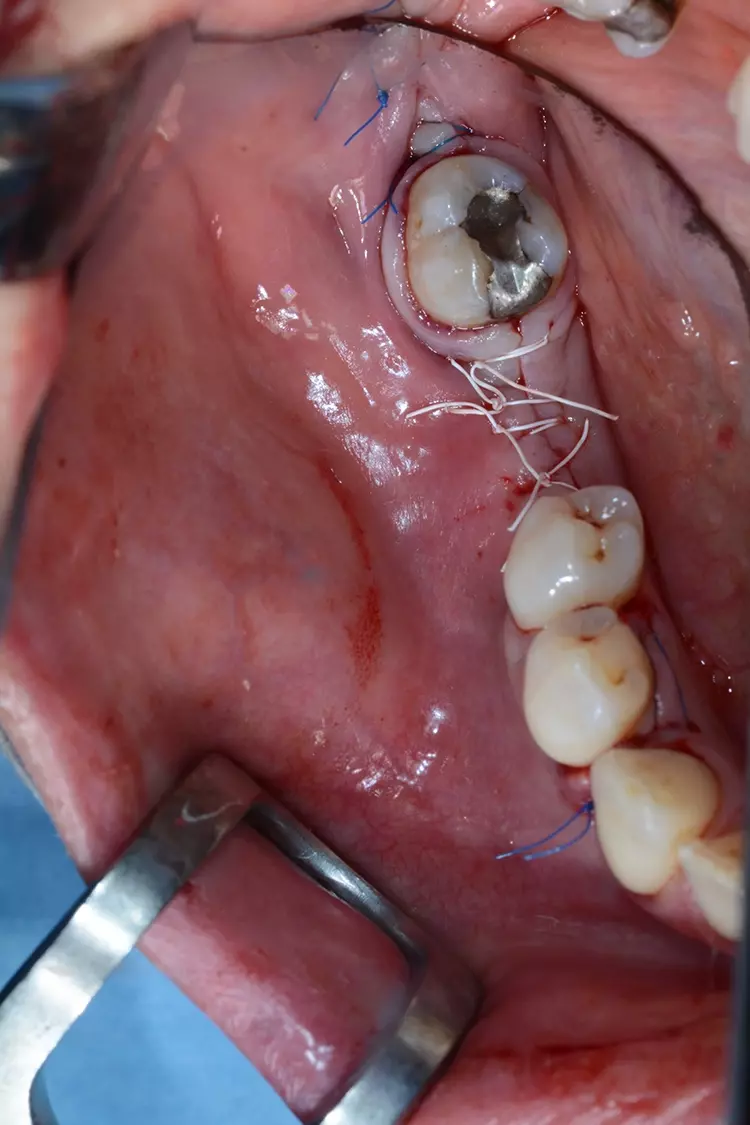

Der Wundbereich wurde mit monofilem, nicht resorbierbarem Nahtmaterial durch eine Kombination aus Rückstich- und Einzelknopfnähten vernäht (Abb. 6). In der klinisch postoperativen Kontrolle nach vier Wochen zeigte sich die Wundheilung komplikationslos (Abb. 7).